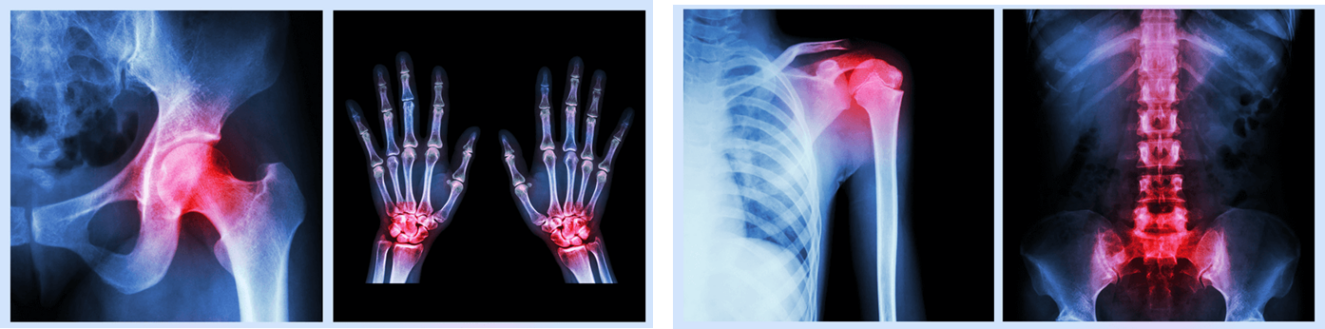

根据研究报道,我国2019年60岁以上人口占总人口超过30%,骨质疏松的患病率为27.8%,其中女性患病率较男性更高,达到惊人的32.1%。骨质疏松会导致骨量大量丢失,使老年人骨头变“脆”,容易导致骨折,进而轻微外伤就会造成脆性骨折,并往往发生在股骨颈、脊柱、腕肩关节等活动较多的部位。